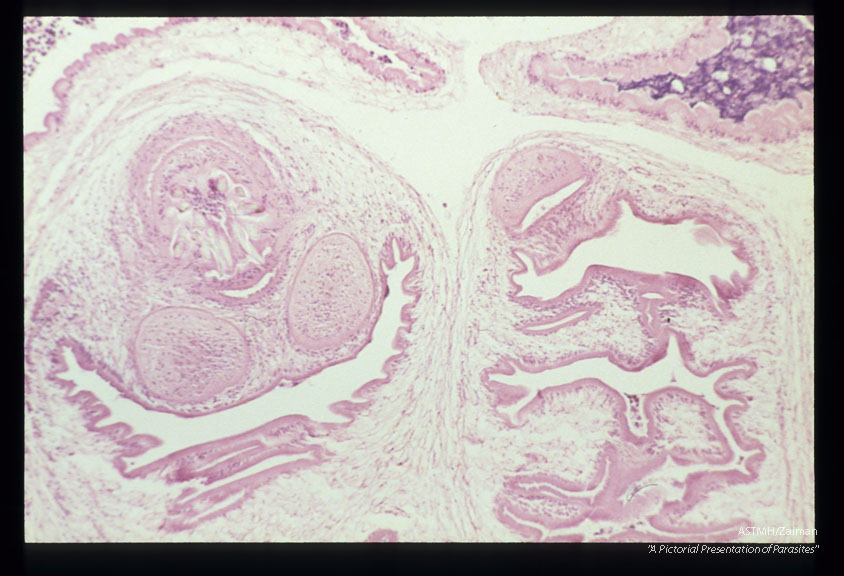

Multiple sections showing membranes, suckers and hooks.

Multiceps

Description: Multiple sections showing membranes, suckers and hooks.